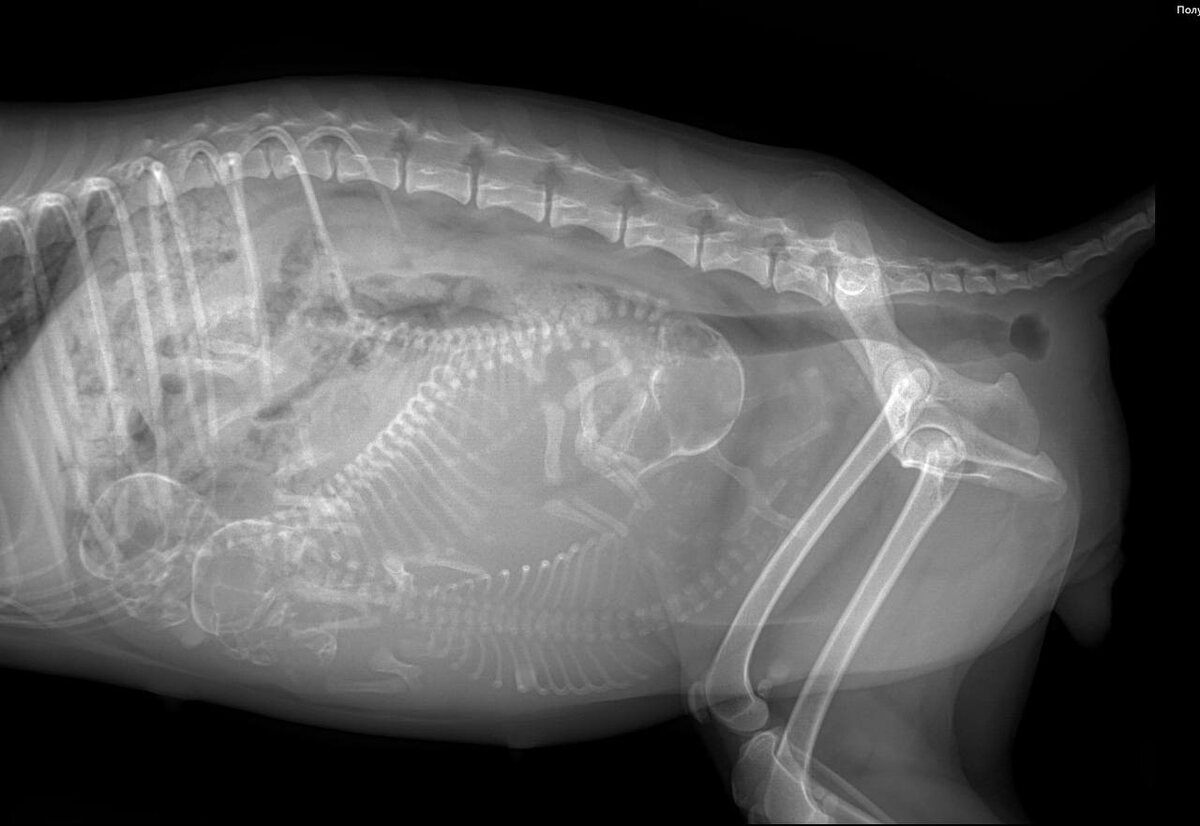

Пациент - собака, породы миниатюрный пудель.

Владельцы были крайне удивлены, когда по результатам клинического осмотра, УЗИ и рентгенографии доктор выявил многоплодную беременность, причем дата предполагаемых родов совпала с днем обращения.

Было принято решение о проведении операции - кесарево сечение.

Таким образом на свет появилось трое здоровых щенков. Мама с малышами в этот же день были выписаны домой.